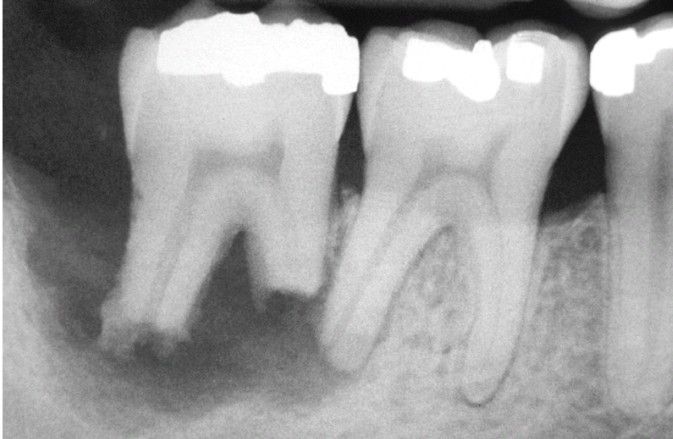

External resorption

Extensive irregular destruction of both roots of the mandibular second molar associated with chronic periodontitis. (Courtesy of Dr. Tommy Shimer.)